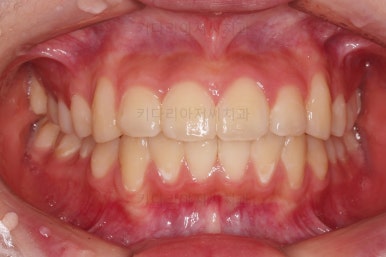

연산동치과 전후사진을 비교해 볼게요.

치열이 가지런해지고 교합도 좋아지고 웃는 모습도 매우 좋아졌네요.

비발치 덧니교정이었지만 입이 튀어나오거나 하지 않고 오히려 치아 각도나 입매가 약간 디ㅜ로 들어가면서 입매도 자연스러워졌어요.

충치치아도 깨끗한 치료가 되었고요.

이상 덧니가 있었던 환자분의 비발치 교정치료 및 신경치료된 충치치아의 크라운 치료를 병행한 연산동치과 치료사례였습니다.